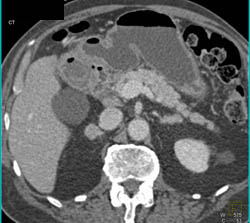

Neuroendocrine Tumor With Nodes Near IVC